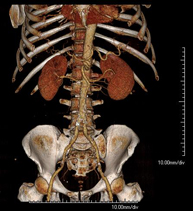

Prova diagnòstica que consisteix en l'estudi de l'abdomen d'alta definició anatòmica (fetge, vesícula biliar, via biliar, pàncrees, melsa, estómac, intestins, ronyons, estructures vasculars, bufeta, úter i ovaris, etc.) mitjançant l'ús d'un equip de TC (Tomografia Computeritzada). Aquestes imatges s'estudien posteriorment en una estació de treball que permet obtenir reconstruccions bidimensionals en diferents plànols de l'espai i també reconstruccions 3D (volumètriques). La majoria d'estudis requereixen l'ús de contrast iodat per millorar la definició de les imatges. - TC Pelvis

Prova diagnòstica que consisteix en obtenir imatges bi i tridimensionals de l'abdomen d'alta definició anatòmica (estructures òssies, estructures vasculars, fetge, pàncrees, vesícula biliar, ronyons, glàndules suprarenals, melsa, intestí prim i gros, bufeta, úter i ovaris, pròstata i vesícules seminals, urèters, etc.) mitjançant l'ús d'un equip de TC (Tomografia Computeritzada). La majoria d'estudis requereixen l'ús de contrast iodat. - TC Fetge

Prova diagnòstica no invasiva que consisteix en l'estudi de l'artèria aorta abdominal a través de l'obtenció d'imatges d'alta definició anatòmica mitjançant l'ús d'un equip de TC (Tomografia Computeritzada) i de contrast iodat. La qualitat de les imatges permet realitzar reconstruccions en 2D i 3D gràcies a estacions de treball especialitzades en l'estudi arterial. Està indicat en aquells pacients amb malaltia vascular (arteriosclerosi), en aneurismes d'aorta, en pacients amb dolor abdominal de possible origen vascular, en estudis prequirúrgics de lesions adjacents a l'aorta abdominal com a "mapa" vascular. La informació obtinguda de manera no invasiva és indispensable per als pacients que requereixen tractament percutani o quirúrgic. En aquells pacients que només requereixen seguiment de les lesions vasculars, aquesta tècnica és la tècnica no invasiva d'elecció juntament amb l'angio-RM. - Angio-TC Artèries renals

Prova diagnòstica no invasiva que consisteix en l'estudi de les artèries renals a través de l'obtenció d'imatges d'alta definició anatòmica mitjançant l'ús d'un equip de TC (Tomografia Computeritzada) i de contrast iodat. La qualitat de les imatges permet realitzar reconstruccions en 2D i 3D gràcies a estacions de treball especialitzades en l'estudi arterial. Està indicat en aquells pacients amb malaltia vascular (arteriosclerosi), en aneurismes d'aorta, en pacients amb dolor abdominal de possible origen vascular, en estudis prequirúrgics de lesions adjacents a l'aorta abdominal com a "mapa" vascular. La informació obtinguda de manera no invasiva és indispensable per als pacients que requereixen tractament percutani o quirúrgic. En aquells pacients que només requereixen seguiment de les lesions vasculars, aquesta tècnica és la tècnica no invasiva d'elecció juntament amb l'angio-RM. - Angio-TC Aorto-ilíac

Prova diagnòstica no invasiva que consisteix en l'estudi de les artèries ilíaques i l'aorta abdominal a través de l'obtenció d'imatges d'alta definició anatòmica mitjançant l'ús d'un equip de TC (Tomografia Computeritzada) i de contrast iodat. La qualitat de les imatges permet realitzar reconstruccions en 2D i 3D gràcies a estacions de treball especialitzades en l'estudi arterial. Aquesta prova està especialment indicada com estudi prequirúrgic (mapa vascular) abans d'intervencions percutànies o quirúrgiques d'aorta abdominal, com l'estudi complementari en pacients amb isquèmia de membres inferiors, etc. - Colonoscòpia virtual